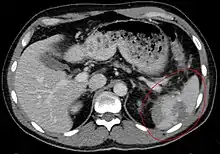

| Spleen ruptured by trauma | |

Splenic rupture is usually evaluated by FAST ultrasound of the abdomen.[3] Generally this is not specific to splenic injury; however, it is useful to determine the presence of free floating blood in the peritoneum.[3] A diagnostic peritoneal lavage, while not ideal, may be used to evaluate the presence of internal bleeding a person who is hemodynamically unstable.[4] The FAST exam typically serves to evaluate the need to perform a CT scan.[4] Computed tomography with IV contrast is the preferred imaging study as it can provide high quality images of the full peritoneal cavity.[3]